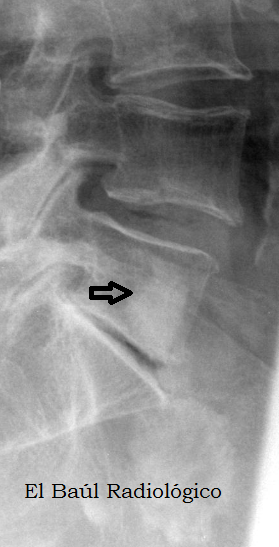

FIGURA 4) El islote óseo se aprecia en una radiografía convencional de la columna lumbar.

(The bone island is also seen in a conventional radiography of the spine).